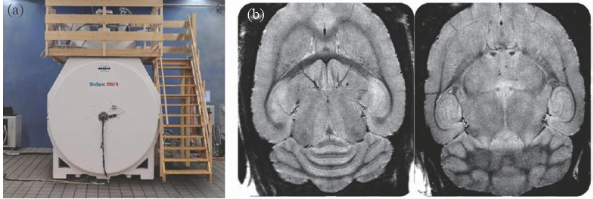

除了人體成像的超高場(chǎng)磁共振成像裝置外,用于動(dòng)物臨床前應(yīng)用的裝置在磁場(chǎng)強(qiáng)度上遠(yuǎn)遠(yuǎn)走在了前面,10 年前就出現(xiàn)了16.4 T/26 cm動(dòng)物成像MRI 機(jī),德國(guó)的Bruker公司在幾年前也推出了更高磁場(chǎng)的動(dòng)物成像機(jī)—— 21 T/11 cm動(dòng)物成像MRI機(jī)(圖8)。

圖8 (a)21 T MRI磁體;(b)大鼠的腦部高分辨率成像(分辨率26 μm)